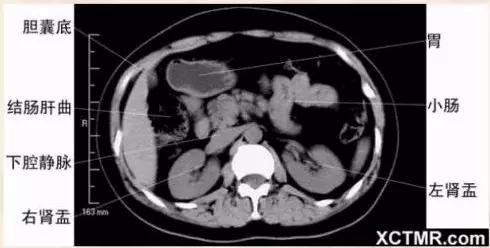

腹部CT